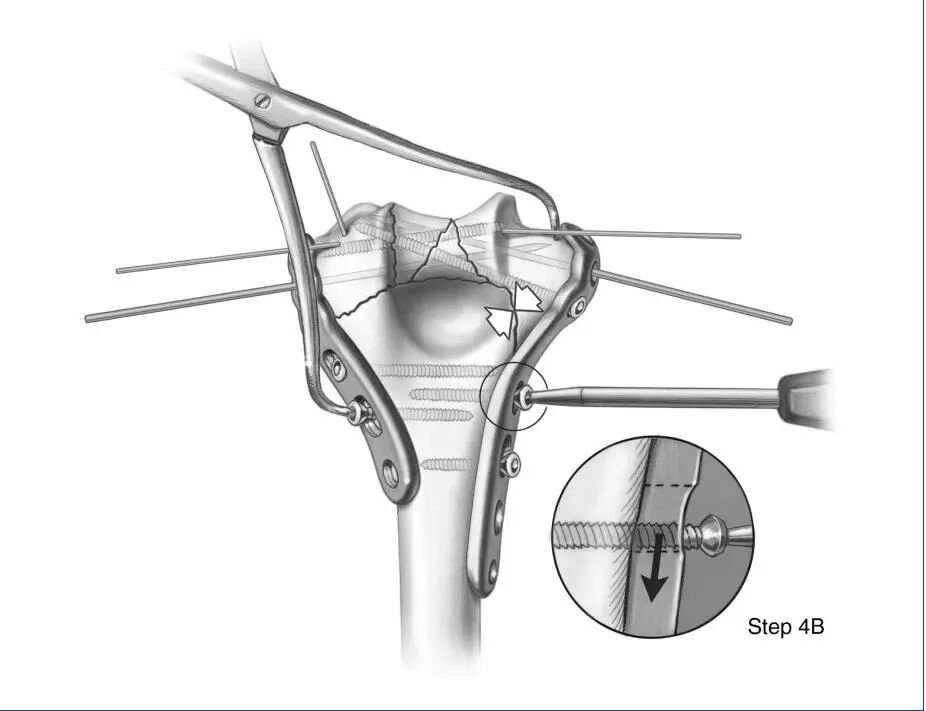

第四步B:以类似的方式使用大复位钳对内侧柱进行加压,并在动态压缩模式下将螺钉插入内侧钢板。如果钢板的轮廓略微欠佳,可以用大骨夹将其压在干骺端上,进一步压缩髁上。